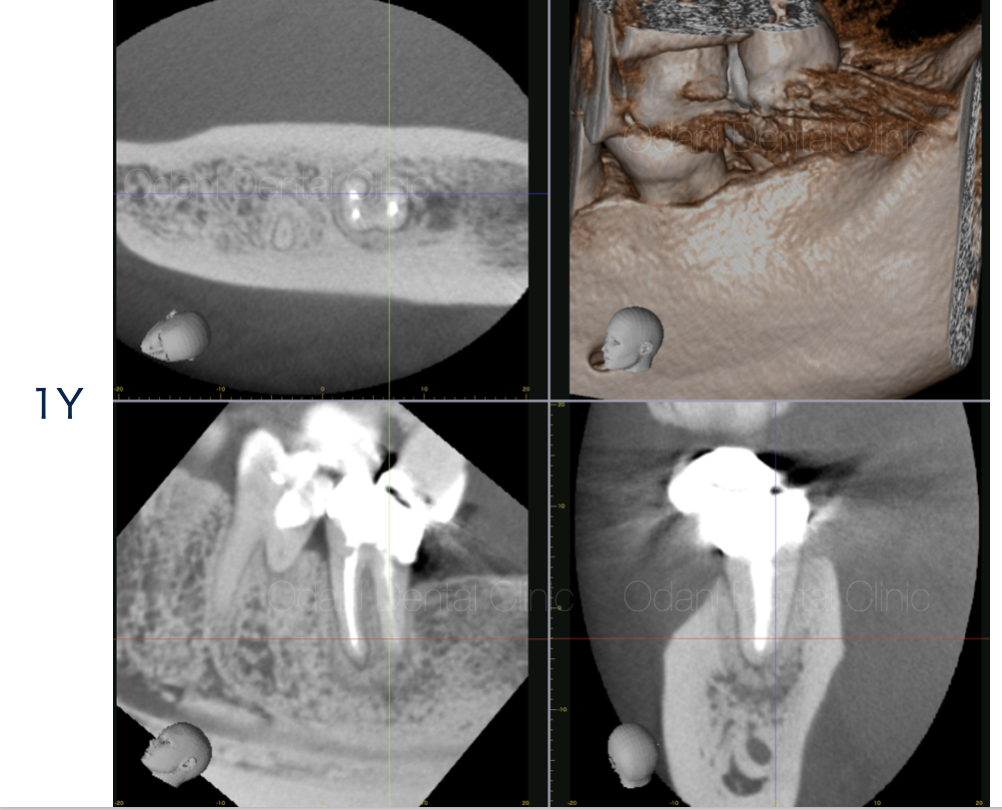

CT画像では、歯の根の周囲の骨が大きく吸収していることが確認でき、それに伴い歯ぐきの腫れや、歯周ポケットが10mm以上と深い状態になっていました。

術後1年の評価にCT撮影を行いましたが、完全な治癒を認めることができました。